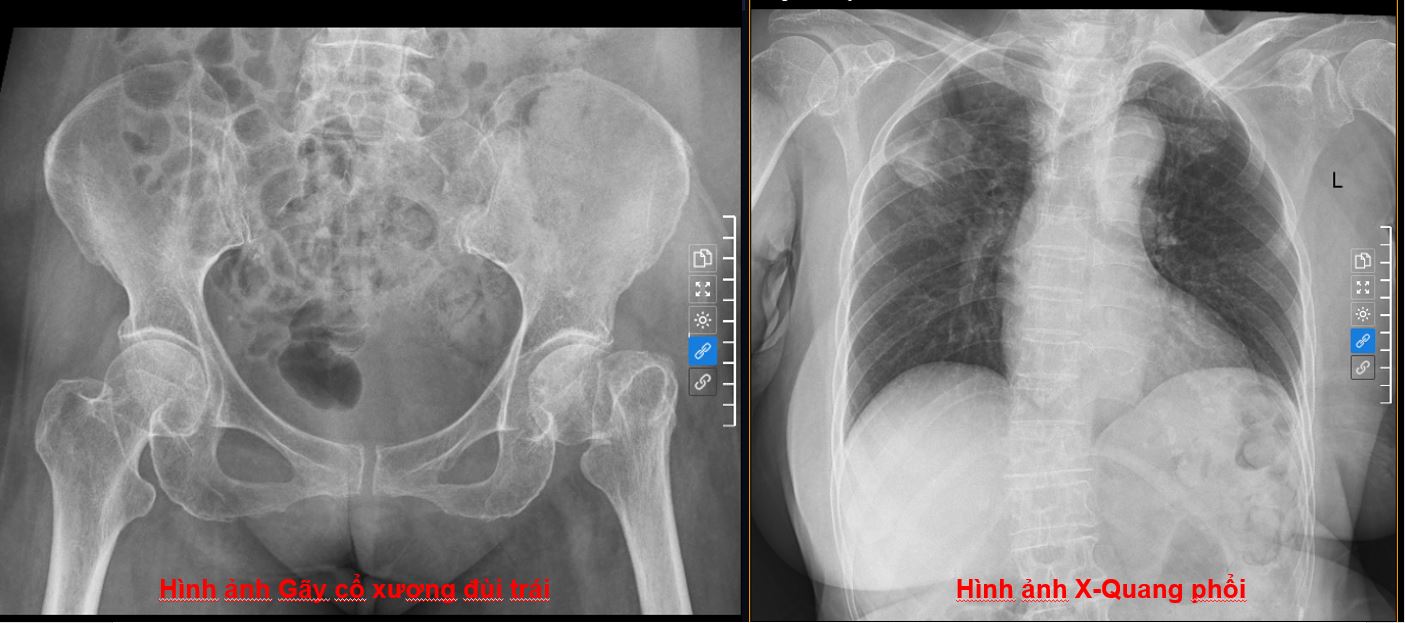

Tỷ lệ tử vong tới 30% sau gãy cổ xương đùi ở người cao tuổi: Vì sao cần điều trị sớm?- Ảnh 1.

Hình ảnh phim chụp X-Quang gãy cổ xương đùi trái và chụp X-Quang phổi của bệnh nhân.